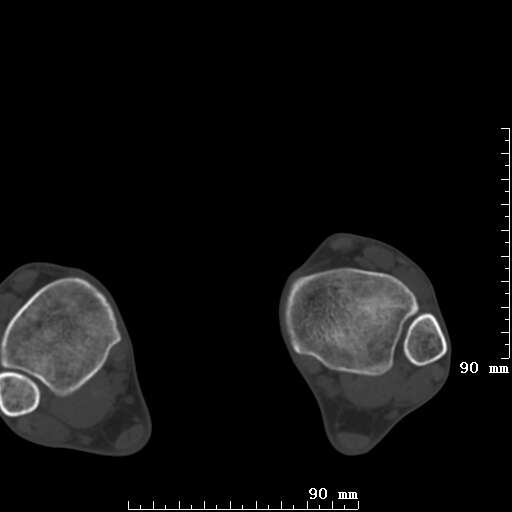

标题: CT19820:外伤一天,如何定性.男27Y [打印本页]

标题: CT19820:外伤一天,如何定性.男27Y

排除下创伤性关节炎吧,距骨有些囊变和硬化,周围韧带软组织有些机化、钙化。不是很像距骨无菌性坏死,感觉在关节面上的多,而不是距骨里面。

未见骨折及脱位像。距骨像是剥脱性软骨炎

支持!(踝关节距骨表面囊变和硬化 缺损)

距骨剥脱性软骨炎可能;踝关节创伤性关节炎?

未见明确新鲜骨折改变,距骨剥脱性软骨炎或踝关节创伤性关节炎可能。

距骨像是剥脱性软骨炎

关节周围多发高密度影,要结合病史

距骨像是剥脱性软骨炎。